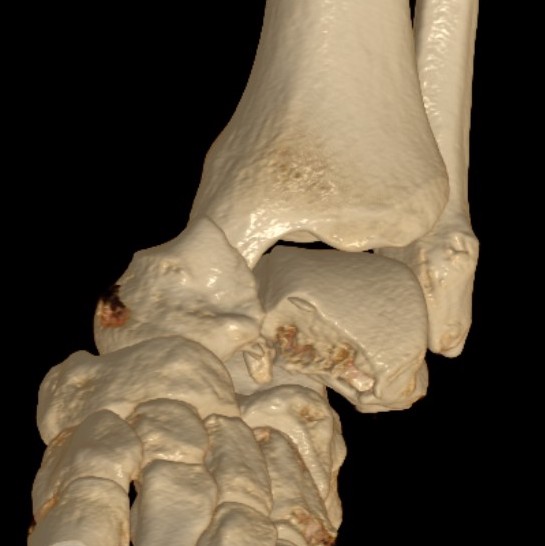

Hawkins classification

Progressive injury

| Type I | Type II | Type III | Type IV | |

|---|---|---|---|---|

| Definition |

Fracture of neck Undisplaced |

Fracture displaces Subluxation / dislocation of the subtalar joint |

Talar body dislocates from ankle joint posteromedially | Talar head dislocates from navicular joint |

| Incidence | 21% | 43% | 31% | 5% |

Type III: Talar body dislocated from ankle joint

Type IV: Talar head dislocated from talonavicular joint